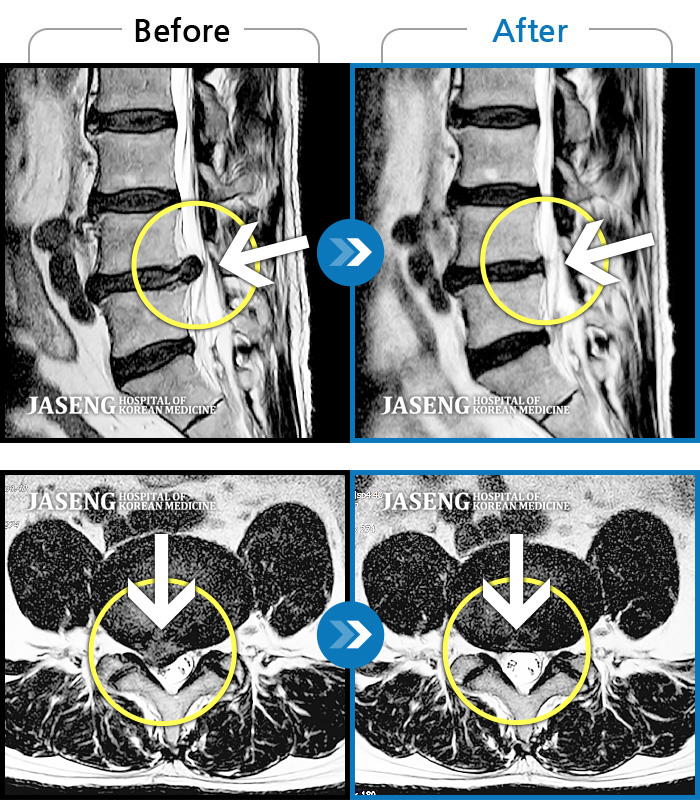

Before

After

허리 골반이 욱신욱신하게 아프고 우측 다리가 저렸다.

2018.03.09 ~ 2020.10.29